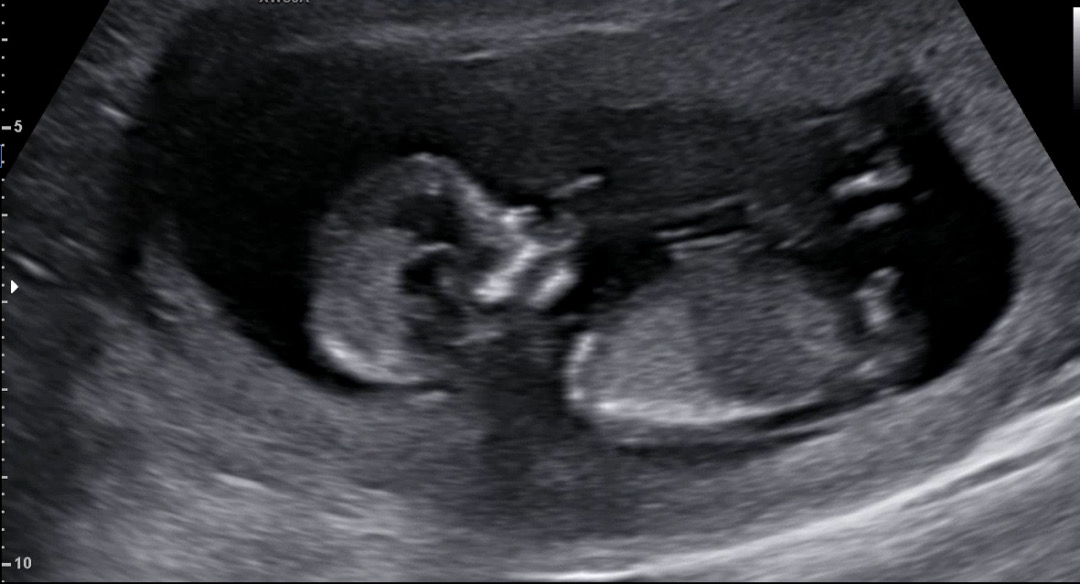

12주3일 각도법!! 성별이 궁금해요ㅋㅋ

아무리봐도 잘 모르겠어요.. 아들인것 같기도 딸인것 같기도.. 끝이 갈라지면 딸이라고 본것같운데.. 갈라져 있는것 같기도 하고.. 각도법 어렵습니다..ㅠㅠ.. 다른분들이 보시기엔 어떠신가요??

다리사이에 삼각점이 보이면 아들이고 작대기 세개가 보이면 딸이라는 글도 봐가지고 더 헷갈렸는데..ㅋ 댓글 달아 주신분들 너무 감사드려요!!